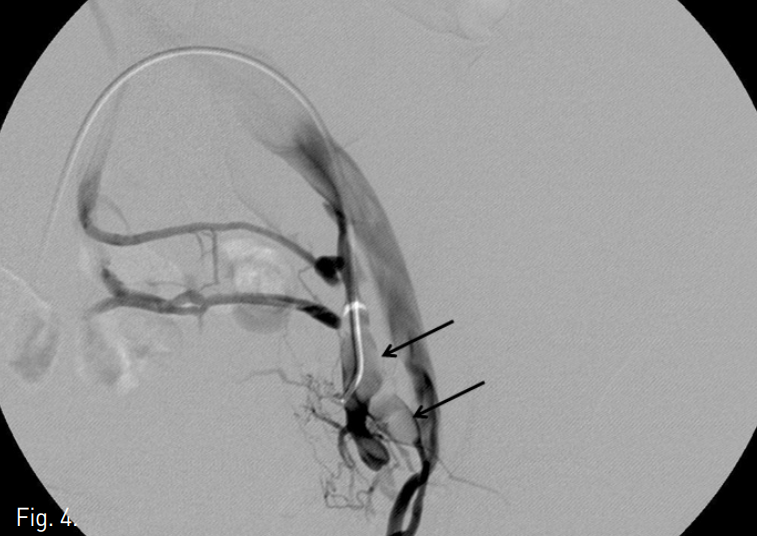

Fig. 2

A, B, C. T2 weighted sagittal MR images and Gadolinium enhanced T1 weighted image demonstrate the mass is growing along the internal iliac vein superiorly (arrows in A, B and C).